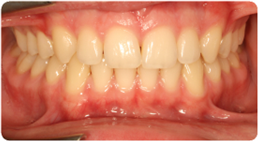

Drag the slider to compare the before and after. This patient presented with severe crowding and overlapping teeth, resolved entirely through BioLign Method-guided aligner treatment.

Overlapping teeth resolved through arch form restoration